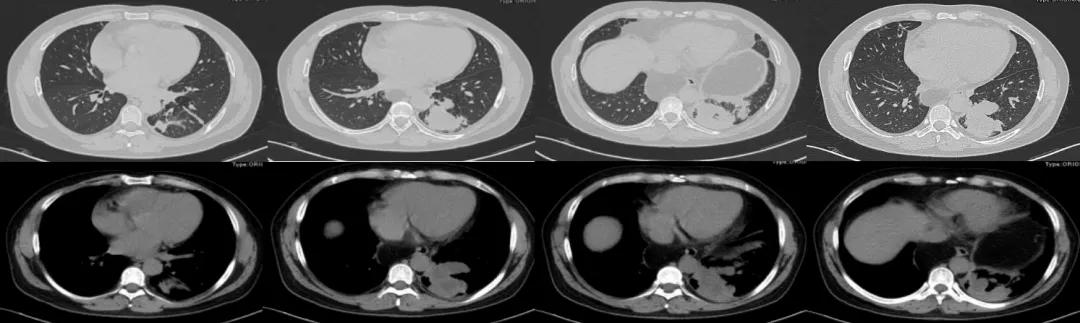

2019年12月5日胸部CT:第一次经皮肺穿刺活检(图2)。

图2:第一次经皮肺穿(2019-12-5)

第一次经皮肺穿刺活检的病理诊断为:肺组织轻-中度慢性炎伴灶区肺泡上皮增生。

2020年5月2日胸部CT:第二次经皮肺穿刺活检(图7),并抽出液化区血性液体(图8)。

图7:第二次经皮肺穿(2020-5-2)

图8:经皮肺穿刺抽出血性液体(2020-5-2)

病理诊断为:肺组织慢性炎,局灶纤维组织增生,慢性炎细胞聚集。穿刺液完善NGS及培养均查见曲霉菌。